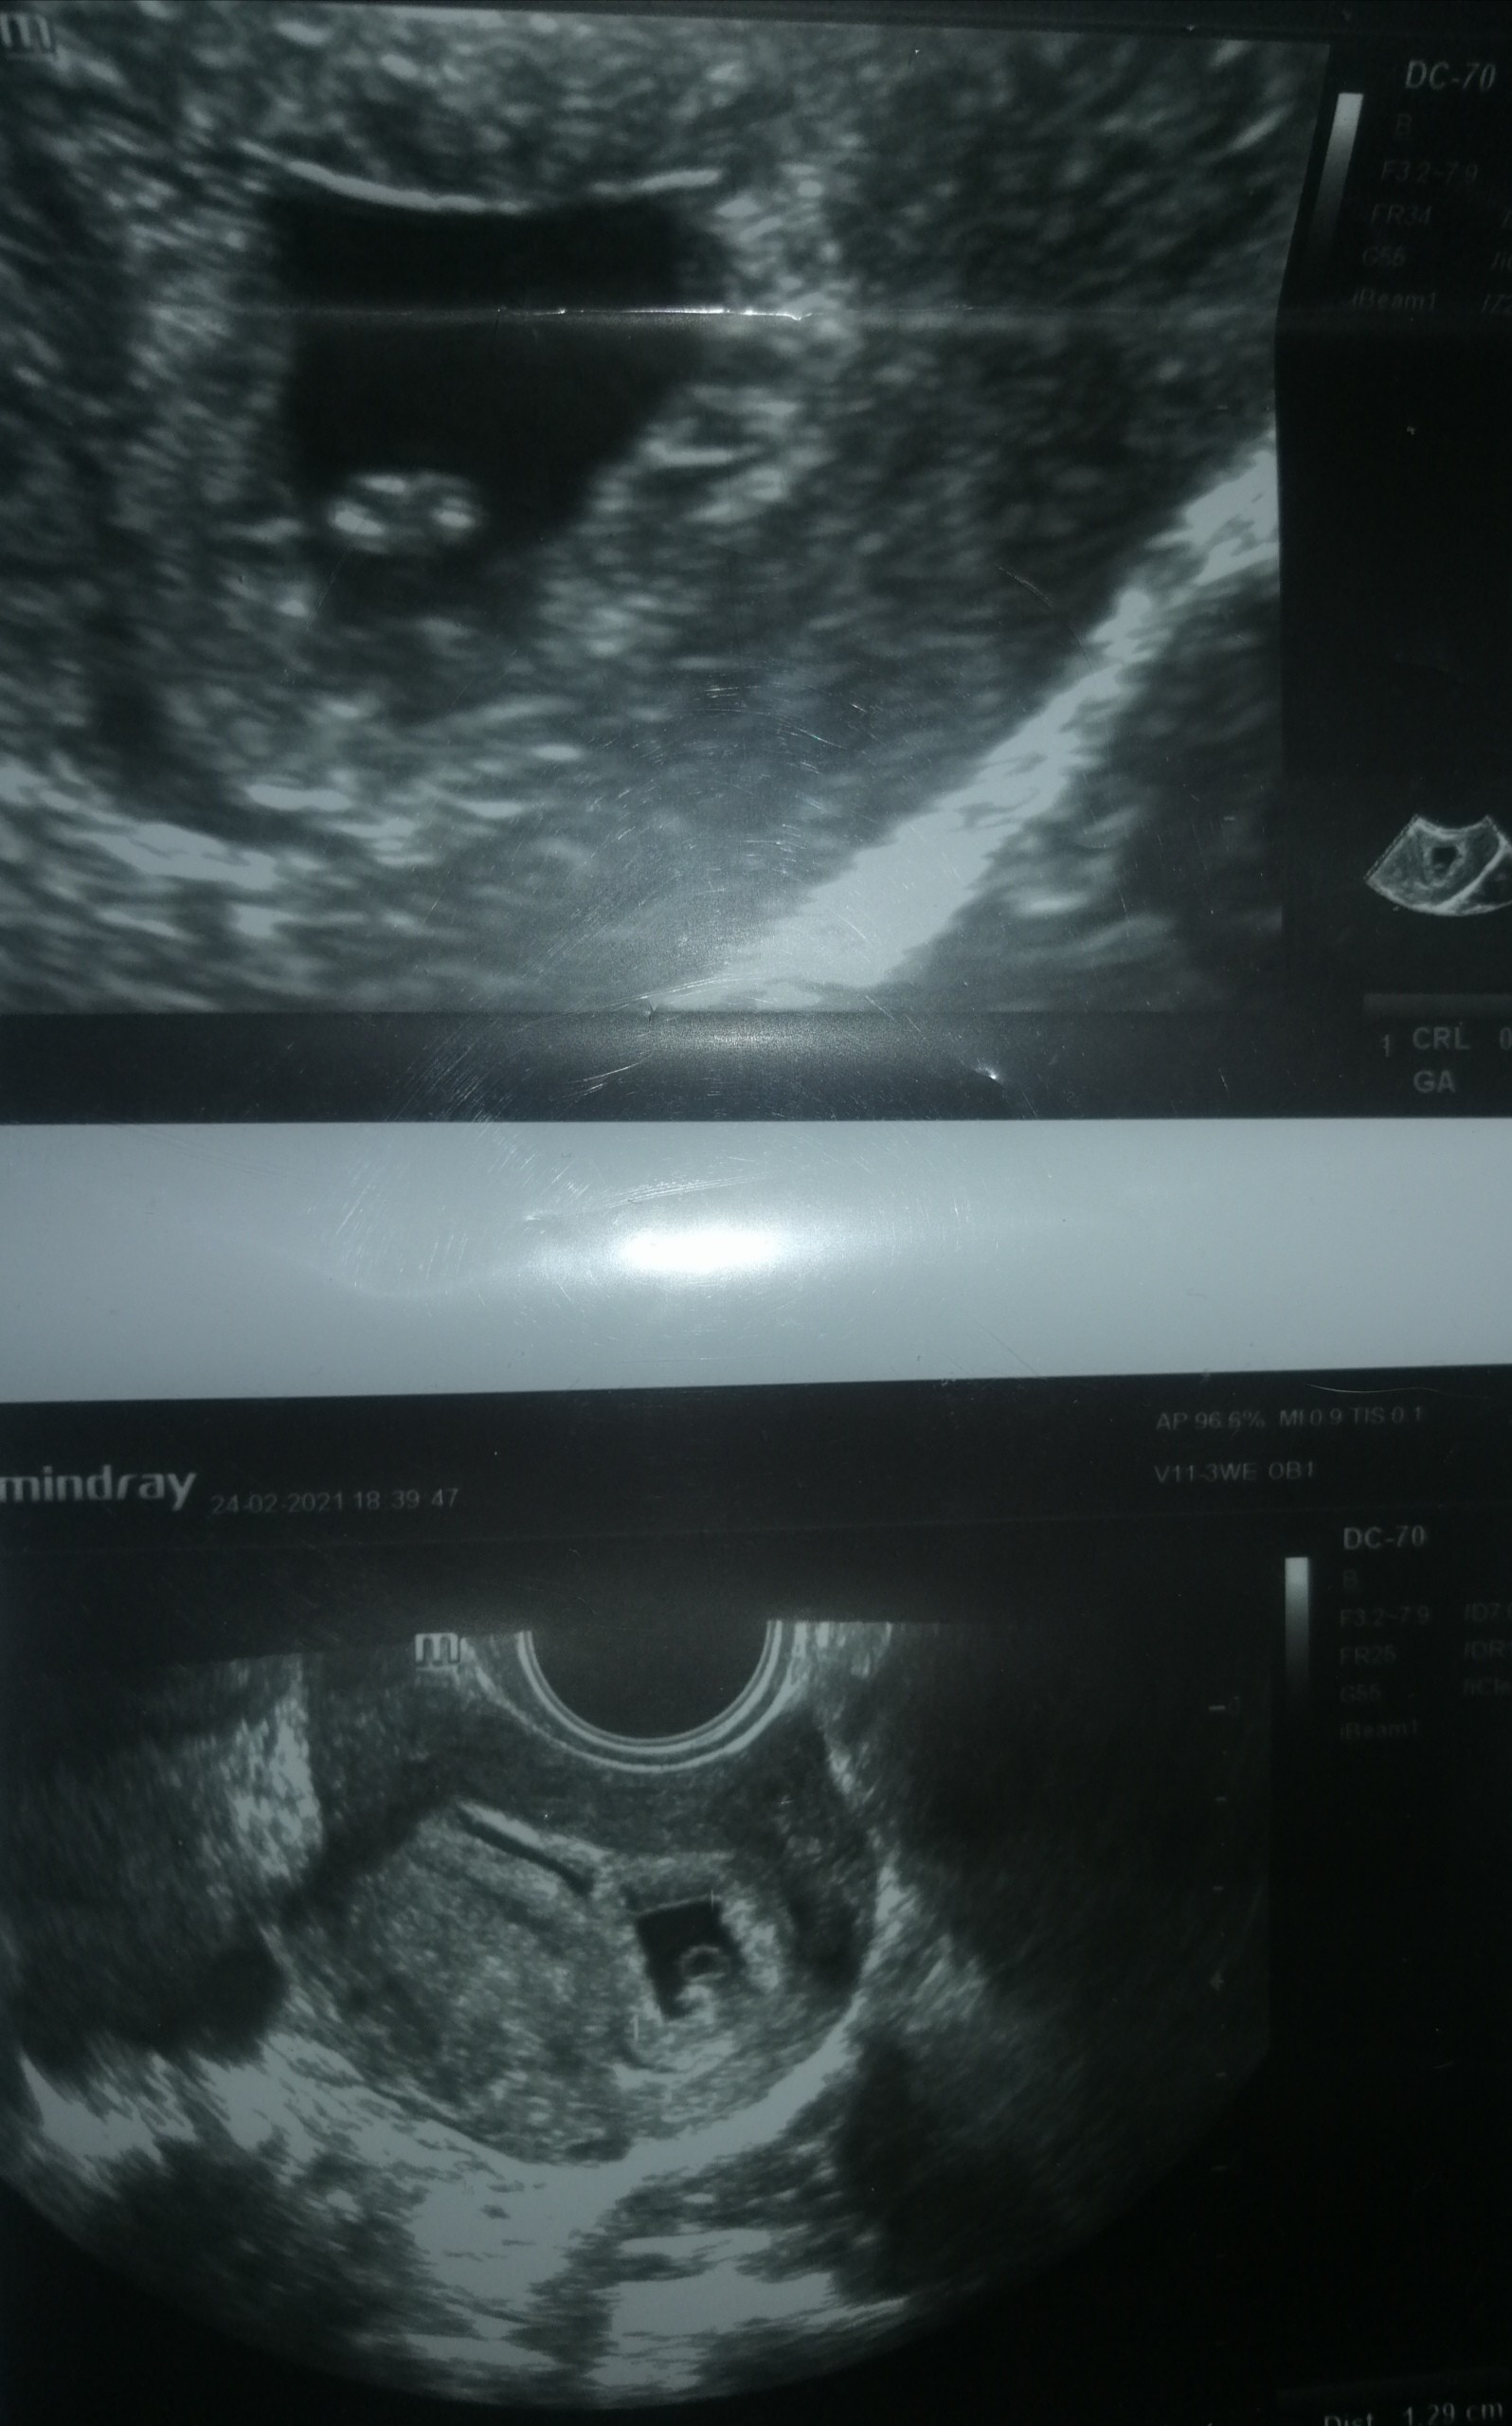

I po wizycie, udało się. Wszystko w porządku. Jest pęcherzyk, jest zarodek i aktywne bijące serduszko. Czyli już pewniej czuje się z Wami :)

Załączniki

• IMG_20210224_175849.jpg